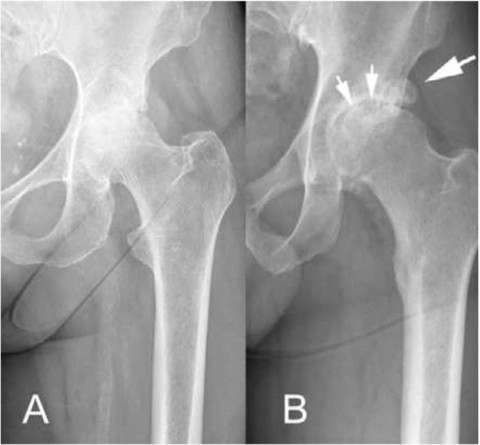

Das Röntgenbild zeigt meist nur eine Gelenkspaltverschmälerung, während klassische Arthrosezeichen, wie Hypersklerose, Osteophyten und Zysten seltener gesehen werden. Die fehlende Sklerosierung der Hüftpfanne und die vorliegende Osteoporose können die Verankerung der Pfanne und des Prothesenschaftes erschweren (Abb. 1). Zudem sind Verdickungen der Gelenkskapsel, wie sie bei einer klassischen Arthrose fast ausnahmslos vorkommen, bei RA deutlich weniger ausgeprägt. Dies führt zu einer sehr guten Beweglichkeit, aber auch zu einem erhöhten Risiko von Luxationen.